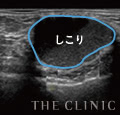

失敗例3

42歳・2ヶ月前に注入

触感が硬いため、ヒアルロン酸を除去したいと来院されたゲストです。エコーによる診察で、乳腺下と皮下に蜂の巣状のしこりが確認できました。近年、このような細かい無数のしこりトラブルが後を絶ちません。当院ではエコーでしこりの位置とサイズを目視しながら、ヒアルロニダーゼという溶解液で溶かして治療しています。